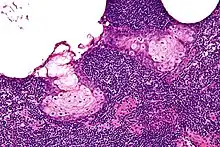

High magnification micrograph of a sebaceous lymphadenoma. H&E stain.

Sebaceous lymphadenoma is a benign tumour of the salivary gland.[1]